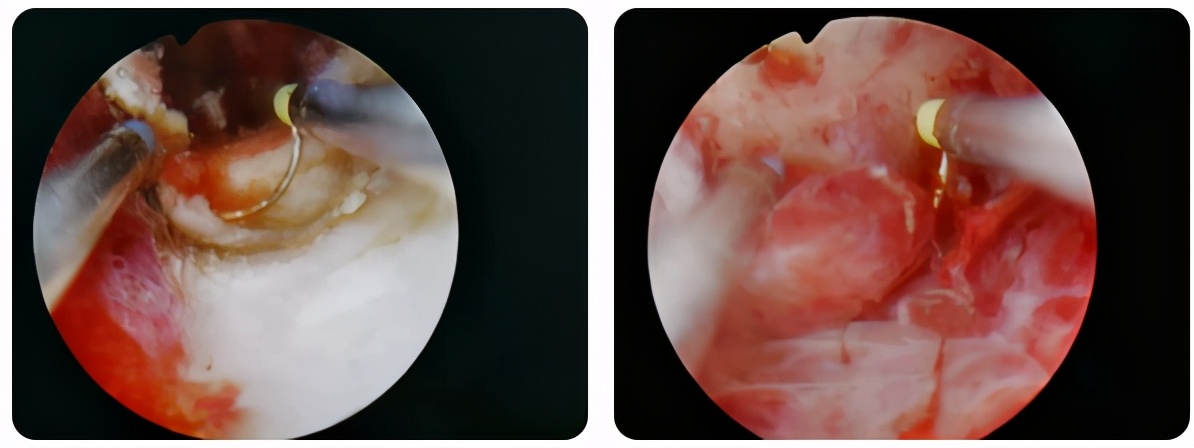

春节前,门诊来了一位身高体胖的患者,进门坐定后便风风火火、一脸焦虑地说:“大夫,我阴道出血好长时间了,量不多但一直不干净,眼看快过年了,我想治治,不能拖着过年呀!”。门诊医生赶忙安慰说:“不要着急,咱们先做个妇科彩超看看是什么情况”。很快彩超回报:宫颈多发那氏囊肿,双附件区未见明显异常,子宫内膜厚度0.4cm。医生进一步分析病情:患者40岁,未生育,有肥胖、高血压、糖尿病等多个子宫内膜癌的高危因素,建议患者先行诊断性刮宫术,进而再明确子宫内膜是否存在病变。在与患者充分沟通后,患者同意了该手术方案,并并很快住院并进行了诊刮术。

术后四天,病理结果回报:(宫腔)子宫内膜单纯性增生伴复杂性非典型增生,局部恶变,而这个“恶变”意味着病情已经进展到子宫内膜癌。当患者听到是恶性肿瘤时,就惊呆在了当场,一种手足无措的样子,让人看着心疼。主诊医生十分理解患者此时的心情,在与患者进行安抚沟通后,她很快镇静了下来。医生在进行了充分术前检查、术前讨论和手术方案的沟通后,患者决定遵照医生的建议进行手术,并决定在我院进行手术治疗,她说她相信西青医院的医疗水平。

患者既往高血压3级、2型糖尿病,空腹血糖最高达16.4mmol/l,餐后血糖最高达25.6mmol/l;肝功能显示两项酶均高于正常值三倍以上,两项蛋白也均异常,腹部彩超提示脂肪肝;下腹部MRI显示子宫峡部内膜明显不规则增厚,符合子宫内膜癌Ia期表现,盆腔、双侧髂血管旁及腹股沟区多发小淋巴结影。随后积极请相关科室会诊,经过妇科、内分泌科、消化科积极联合治疗后,空腹血糖控制在4.3-8.3mmol/l之间,餐后2小时血糖控制在8.2-9.7mmol/l之间,肝功能大致正常,血压、血糖均达到手术安全范围。遂决定对患者行 腹腔镜下 子宫内膜癌全面分期手术:即 筋膜外全子宫切除术+双侧附件切除术+盆腔淋巴结清扫术 。